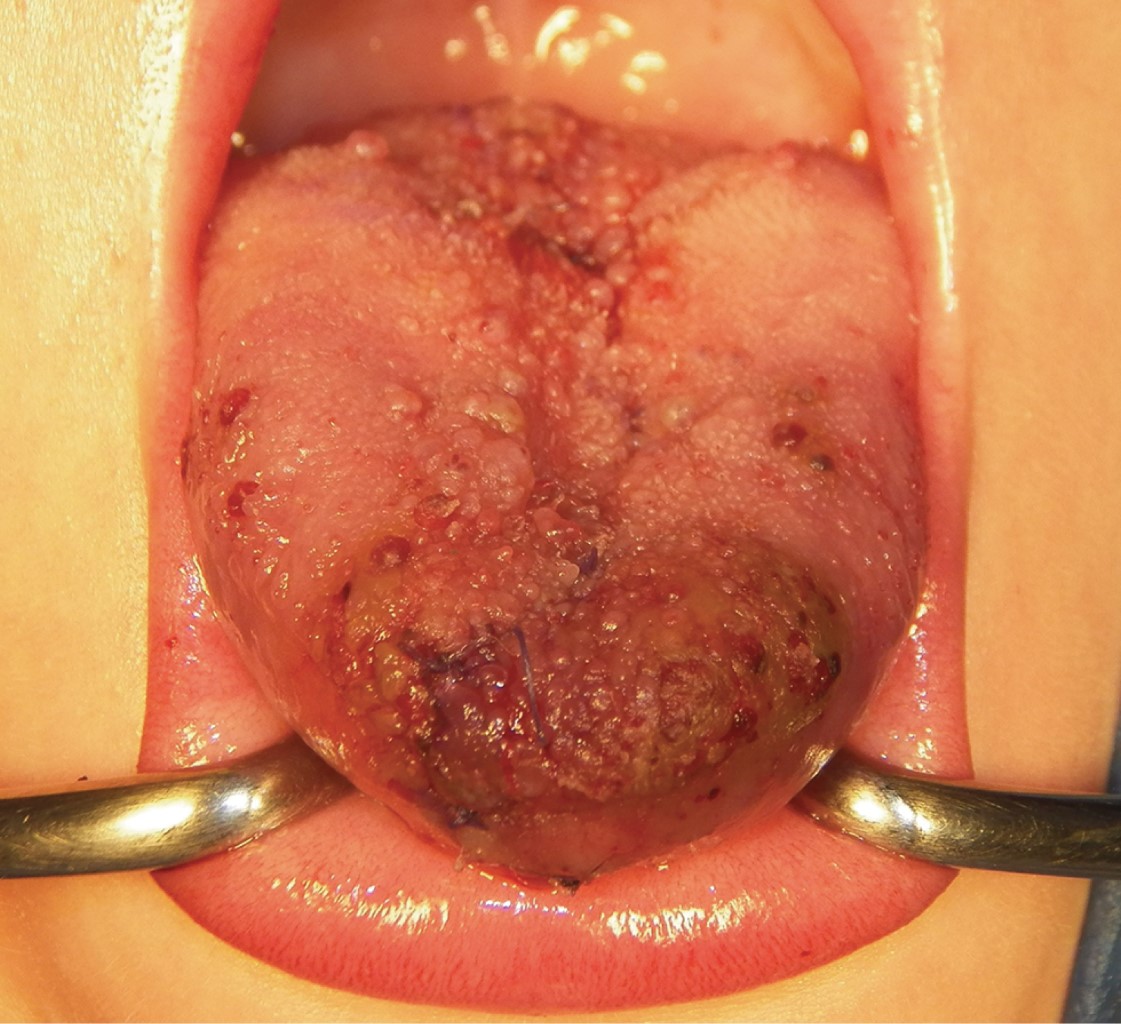

La macroglosia es una afección caracterizada por el aumento del tamaño de la lengua causado por malformaciones congénitas como linfangiomas, corioestomas, hamartomas, o malformaciones adquiridas como neoplasias benignas o malignas. En la mayoría de los casos, el tratamiento es quirúrgico y puede ser conservador cuando la vía aérea no está comprometida. En este trabajo presentamos el caso de un paciente varón de dos años con diagnóstico de macroglosia por linfangioma. El protocolo de tratamiento consistió en una glosectomía parcial mediante la técnica de resección en cuña estelar y colgajo de rotación anterior, así como terapia del habla tras la fase quirúrgica. Tras un año de seguimiento, se observó la persistencia de la lesión, lo que mereció una segunda intervención quirúrgica en la que se consiguió una dimensión lingual de parámetros normales, preservando la armonía estética y funcional sin causar alteraciones neurosensoriales ni gustativas.

Figura 2